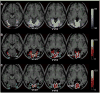

Associative learning is an essential brain process where the contingency of different items increases after training. Associative learning has been found to occur in many brain regions [1-4]. However, there is no clear evidence that associative learning of visual features occurs in early visual areas, although a number of studies have indicated that learning of a single visual feature (perceptual learning) involves early visual areas [5-8]. Here, via decoded fMRI neurofeedback termed "DecNef" [9], we tested whether associative learning of orientation and color can be created in early visual areas. During 3 days of training, DecNef induced fMRI signal patterns that corresponded to a specific target color (red) mostly in early visual areas while a vertical achromatic grating was physically presented to participants. As a result, participants came to perceive "red" significantly more frequently than "green" in an achromatic vertical grating. This effect was also observed 3-5 months after the training. These results suggest that long-term associative learning of two different visual features such as orientation and color was created, most likely in early visual areas. This newly extended technique that induces associative learning is called "A-DecNef," and it may be used as an important tool for understanding and modifying brain functions because associations are fundamental and ubiquitous functions in the brain.